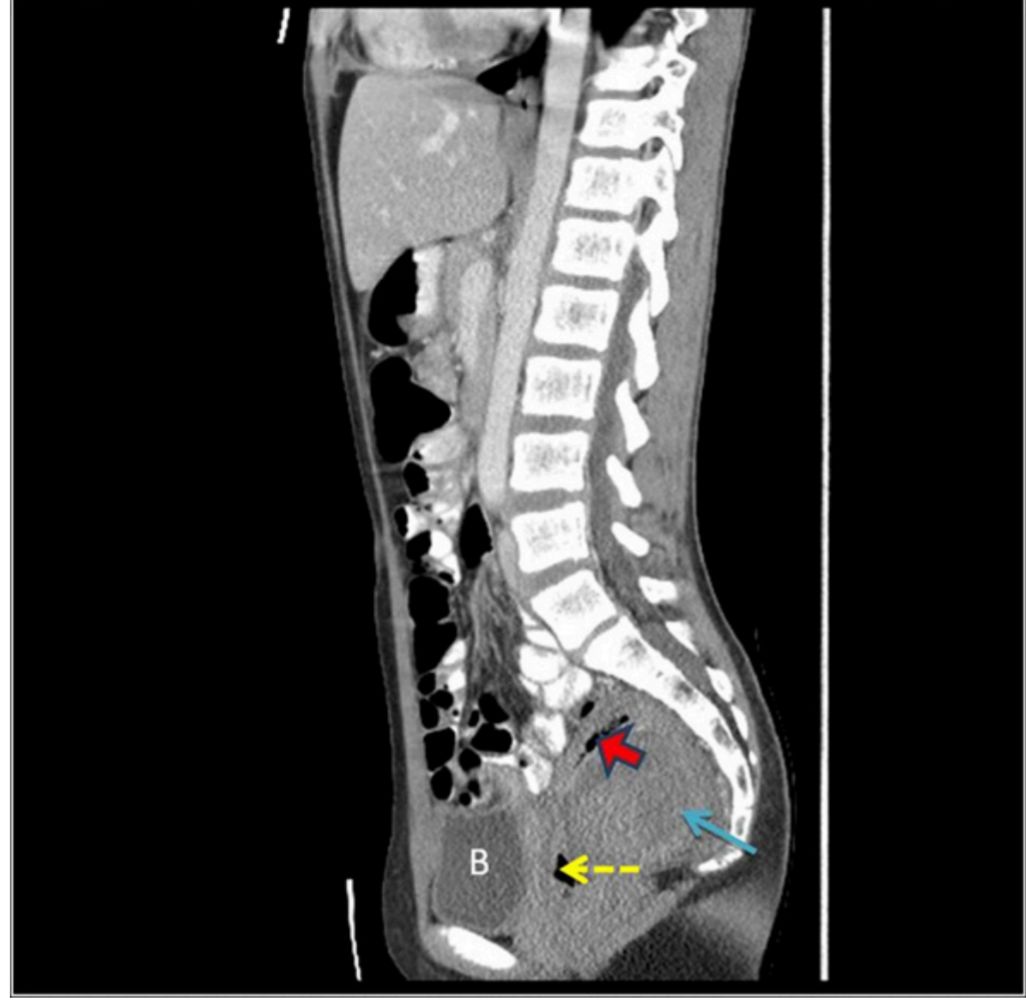

图2为腹部盆腔CT扫描。骶骨前和肛管后的不均匀液体蓄积(蓝色箭头)。液气平(红色箭头)引起肠壁破裂的担忧。B=膀胱。虚线箭头表示直肠腔。